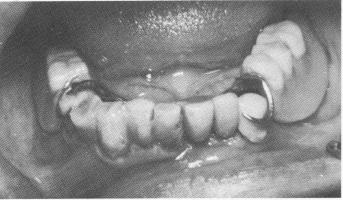

Fig. 13-33. The mouth of a 55-year-old physician.

Fig. 13-34. Three loose teeth were supported with endodontic stabilizers.